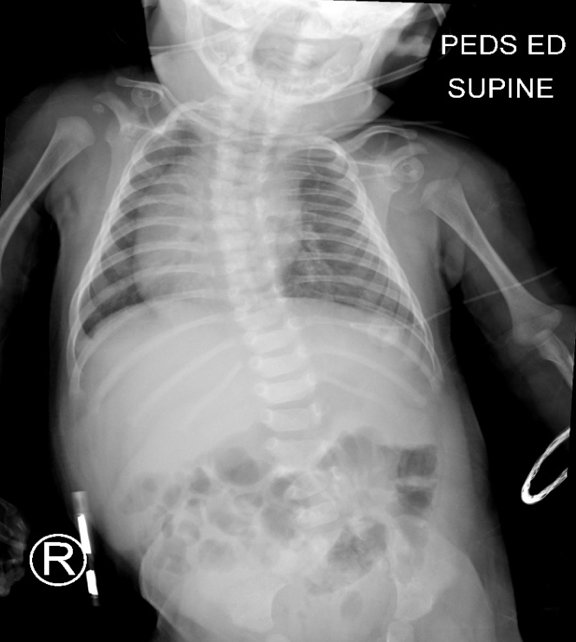

Later, renal ultrasonography results showed obstruction of the right kidney with right renal enlargement and delayed clearance in the dilated right renal pelvis. The smaller left kidney yielded decreased perfusion to the upper pole and a dilated left renal pelvis. Physical examination showed 14 ribs bilaterally with dextroscoliosis, and “butterfly vertebra” at T6. A skeletal survey showed multiple vertebral and rib anomalies and shortening of the first metacarpal bilaterally (Figure 1). Pre- and post-void mercaptoacetyltriglycine-3 (MAG-3) diuretic renal scans showed right renal enlargement and left megaureter (Figure 2).

Figure 1. Radiograph showing multiple congenital abnormalities.

The initial visit with an orthopedist included assessments for torticollis, congenital scoliosis, hip dysplasia, and pes valgus. Anteroposterior (AP) radiographic view of the pelvis revealed evidence of hip dysplasia with asymmetric femoral ossific nuclei, with less ossification on the left than on the right. AP and lateral radiographs of the spine revealed congenital scoliosis with multiple hemivertebrae noted. A pelvic AP view then noted anatomic alignment of all structures. Mild acetabular dysplasia was noted on the left side. AP and lateral radiographs of the spine showed multiple congenital abnormalities, including mild dextroconvex scoliosis of the thoracic spine and dextroconvex lumbar curve. Multiple segmentation abnormalities were present in the upper thoracic spine, T5-6 and 7, at the T9-10 interspace, and at the L3-4 level. There was marked adenotonsillar enlargement, with narrowing of the nasopharyngeal and oropharyngeal airways.